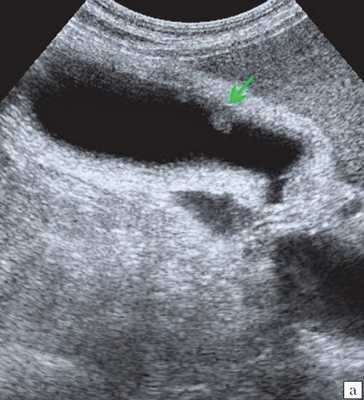

При поступлении в НМИЦ хирургии им. А.В. Вишневского пациентке выполнена фистулохолангиография (рис. 1), - это исследование показало, что тотчас после слияния долевых протоков печени отмечается полный блок общего печеночного протока. По классификации Strasberg с соавт., данную стриктуру можно отнести к типу Е2; по классификации Э.И. Гальперина - к типу «0».

Специальную сверхтонкую струну-проводник удалось провести в сегментарный проток правой доли печени (рис. 2), после чего принято решение первоочередно расширить просвет протока специальными эндоскопическими бужами (рис. 3, 4), постепенно увеличивая диаметр последних.